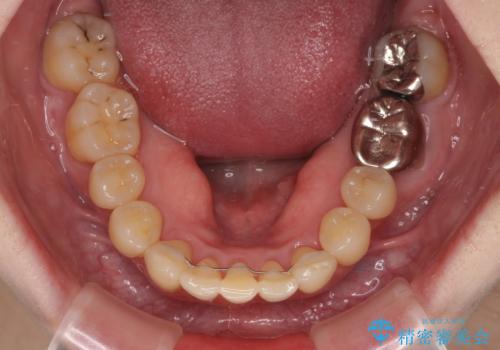

- 八重歯と正中のズレを気にして来院された患者様です。

上顎左側が八重歯になっており、上顎正中が左側にずれていました。

上顎左側の第一小臼歯を抜歯し、補助装置を用いて正中位置を改善しながら八重歯を解消していくこととしました。

下顎前歯が1本欠損していたため、上下正中の位置が合わせるという目標はなく、鼻筋に上顎正中を合わせていくように移動を行いました。